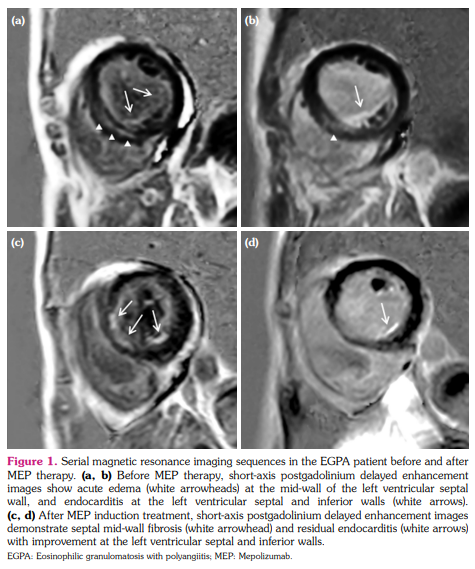

A 36-year-old female presented to our hospital with dyspnea and palpitation that had lasted for one month. Based on bronchial asthma, mononeuritis multiplex, and blood eosinophilia with extravascular infiltration,[6] the patient had received an EGPA diagnosis a year ago. She was in remission under combined CYC/GC induction therapy. At admission, laboratory tests revealed positive antimyeloperoxidase and increased levels of eosinophils (7,140/µL) and cardiac biomarkers. Echocardiography and magnetic resonance imaging demonstrated impaired left ventricular ejection fraction, myocardial edema, and diffuse mid-wall and endocardial enhancement, indicating endomyocarditis with cardiac insufficiency (Figure 1a, b). Holter monitoring revealed paroxysmal atrial tachycardia and atrial/ ventricular premature contractions. Glucocorticoid and cardiac supporting agents were prescribed for the disease relapse with heart involvement. The patient refused CYC induction therapy due to the side effects from earlier exposure. There was a more than 90% decrease in blood eosinophilia with stationary follow-up counts less than 150/µL following subcutaneous injection of 100 mg MEP quadriweekly (i.e. one time every four weeks). Twelve months after therapy, in addition to absent clinical symptoms and normalized biomarker levels, cardiac examinations showed normalized rhythm and left ventricular ejection fraction, resolved myocardial edema, and reduced mid-wall and endocardial delayed gadolinium enhancement (Figure 1c, d). No adverse effects were observed. The patient had a complete remission with sparing daily use of GCs.